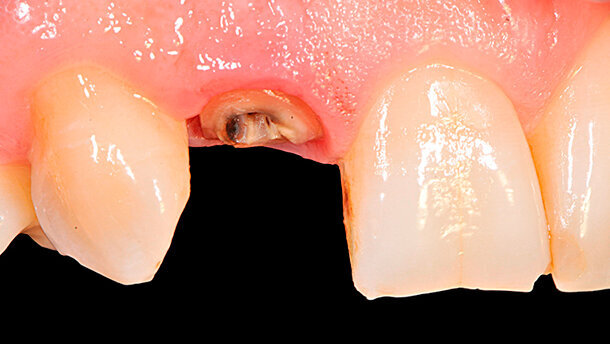

All’E.O. (Fig. 2) si evidenzia un elemento protesico in metal-free del 12 incongruo da un punto di vista estetico e con un processo infiammatorio a livello marginale determinato da una scarsa precisione della corona e il non rispetto dell’ampiezza biologica. L’aspetto radiografico (Fig. 3) evidenzia la presenza di un perno in metallo e una terapia endodontica senza sintomatologia da parte del paziente.

Dopo un colloquio con il paziente sulle diverse possibilità terapeutiche, soprattutto legate all’incognita di non sapere che tipo di moncone dentale residuo avremmo potuto trovare dopo la rimozione della corona, si decide in accordo con il paziente di iniziare la terapia cercando di rispettare una tempistica veloce e non altamente invasiva. Iniziata la terapia, alla rimozione della corona metal-free (Fig. 4) si evidenzia come la presenza del perno in metallo occupi la maggior parte del moncone dentale residuo. Insieme al paziente si valuta la necessità di eseguire una estrusione ortodontica al fine di poter avere un maggior supporto dentale e ripristino dell’ampiezza biologica, come garanzia di stabilità a lungo termine dell’elemento dentario protesico finale.